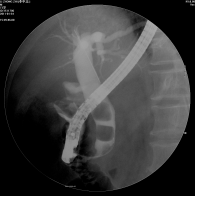

将电子十二指肠镜从口腔插入,通过食管、胃、十二指肠到达十二指肠镜乳头部(胆胰管向十二指肠开口)后,先造影以便准确诊断。然后根据结石大小等具体情况进行十二指肠括约肌切开或扩张、网篮取结石、置鼻胆管引流、置支架等治疗。

1、网篮取石:对<1cm结石均可用网篮取石,在X线监视下将网篮伸过结石,张开网篮,抓取结石后取出